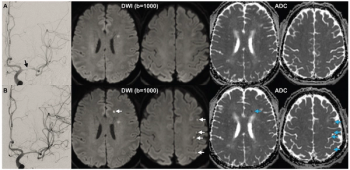

In a recently published review, radiology researchers from the University of Wisconsin discussed the potential and key considerations for applying accelerated magnetic resonance imaging (MRI) protocols in the assessment of emergent and urgent conditions.